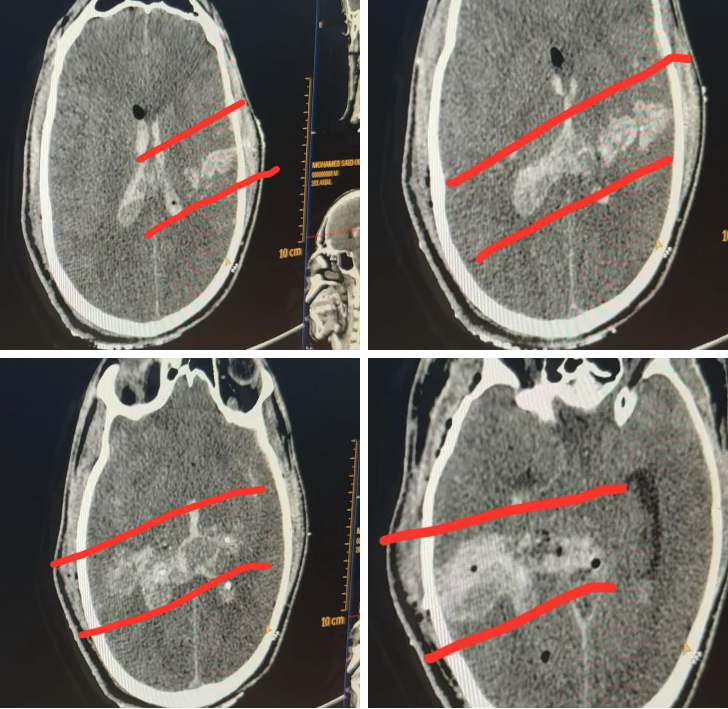

“He was brought in after an airstrike on the Mawasi tent encampment on a day when there were multiple mass casualty incidents. Some young people had been sitting at a makeshift internet cafe, including students studying for tests. Lots of patients had shrapnel injuries, but he had only two wounds, and both were in his head,” said Dr. Mimi Syed, an emergency medicine physician who has completed two medical missions to Gaza. “There was one entry and exit point, and on the CT scan it looks like a clear path. Usually with shrapnel, you’d have pieces of shrapnel still lodged inside the brain, or multiple injuries to the face. He had no other internal injuries, or injuries to other parts of the body that are common with shrapnel.”

Drop Site reviewed CT scans taken from Halimy’s injury as well as video taken of Halimy, unconscious, being intubated and treated by emergency medical personnel at Nasser Hospital. While not conclusive, the information provided suggested a gunshot wound to the head as a possible cause of death. The Israeli military did not respond to a request for comment.

Drop Site shared the scans and video with two medical experts to get secondary assessments.

“If there were no other injuries involved, it would be incredibly rare for a shrapnel injury to have such an isolated trajectory or injury. There should’ve been some other debris embedded in his body elsewhere which they likely would have seen on any x-rays that they did,” said Zain Qazi, a doctor and board certified diagnostic radiologist. “I’ve seen a lot of gunshot wounds to the head that look very similar. Sometimes the bullet is still embedded in the soft tissues or the skull, and shrapnel very likely would also have embedded itself somewhere in the bony structure or soft tissues. Oftentimes with smaller caliber bullets the bullet will fragment and have small metallic debris in the head, which we don’t see here.”

“These scans are highly suspicious of a gunshot wound to the head,” he added.

“The trajectory is really suspicious to be that precise,” added Nabeel Rana, another American doctor who had participated on past medical missions to Gaza. “Having said that, the typical sniper bullets we would see in these isolated gunshots would use larger calibre bullets so the exit wounds were usually pretty large.” The video, he said, did not show a clear enough view of the exit wound on Halimy’s head to make a conclusive determination, and that some small single shrapnel wounds had killed people in Gaza in his experience.